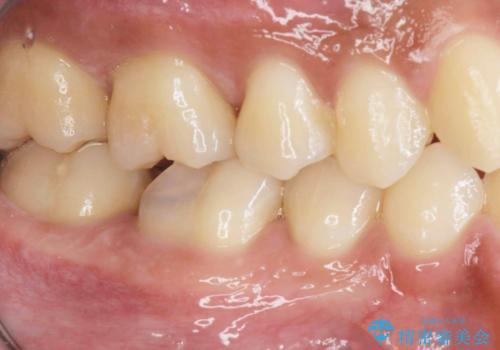

3. 放置してしまった虫歯の治療の治療後